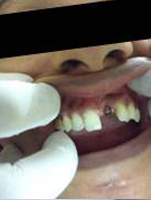

Drilled socket for Implant

Single Tooth Implant